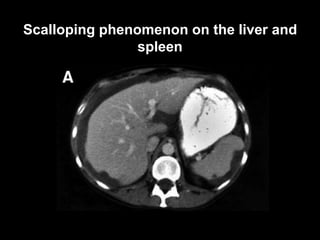

Pseudomyxoma peritonei (PMP) is a rare condition characterized by gelatinous ascites resulting from the rupture of appendiceal mucinous tumors, leading to significant abdominal complications. The incidence is approximately 2 cases per million per year, with a predominance in females, and diagnosis often relies on imaging techniques like ultrasound and CT scans. Effective treatment involves cytoreductive surgery combined with hyperthermic intraperitoneal chemotherapy (HIPEC) to manage disease progression and improve outcomes.